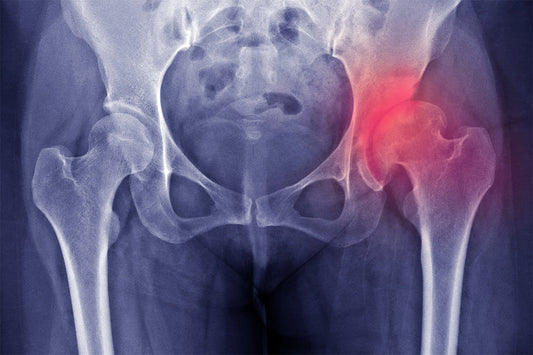

Hip fracture

Hip dysplasia